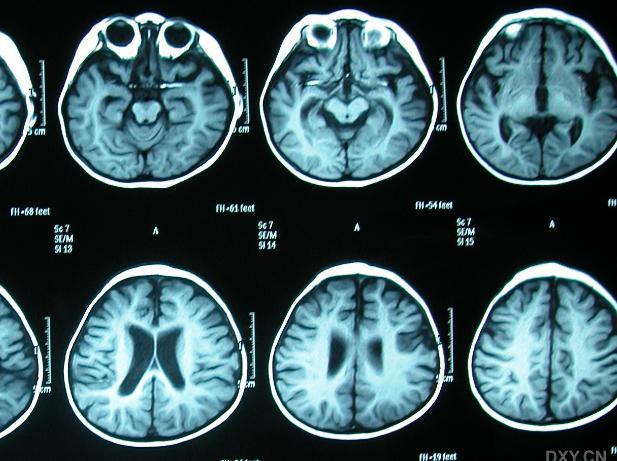

颅脑磁共振

颅脑磁共振这项先进的影像技术 , 不仅具备极高的分辨率和精准的定位能力 , 更能在无创伤的前提下 , 深入探索人脑的内部结构 。

颅脑磁共振成像技术的诞生 , 开启了神经科学研究的新篇章 , 为众多神经系统疾病的诊断提供了强有力的支持 。

颅脑磁共振通过捕捉脑部组织的微妙变化 , 能够精准地反映出脑部疾病的病理过程 。 无论是脑梗塞、脑出血 , 还是脑肿瘤、脑炎等神经系统疾病 , 颅脑磁共振都能以其独特的视角 , 为医生提供详尽的病变信息 。

医生们可以依据这些图像 , 对病情进行准确判断 , 从而制定出更为科学合理的治疗方案 。 此外 , 颅脑磁共振在脑外伤、脑退行性疾病等领域也发挥着不可替代的作用 。

它不仅能够发现脑部结构的微小变化 , 还能通过功能成像技术 , 揭示脑部功能的异常 。 这使得医生们能够更全面地了解患者的病情 , 为患者提供更为个性化的治疗方案 。